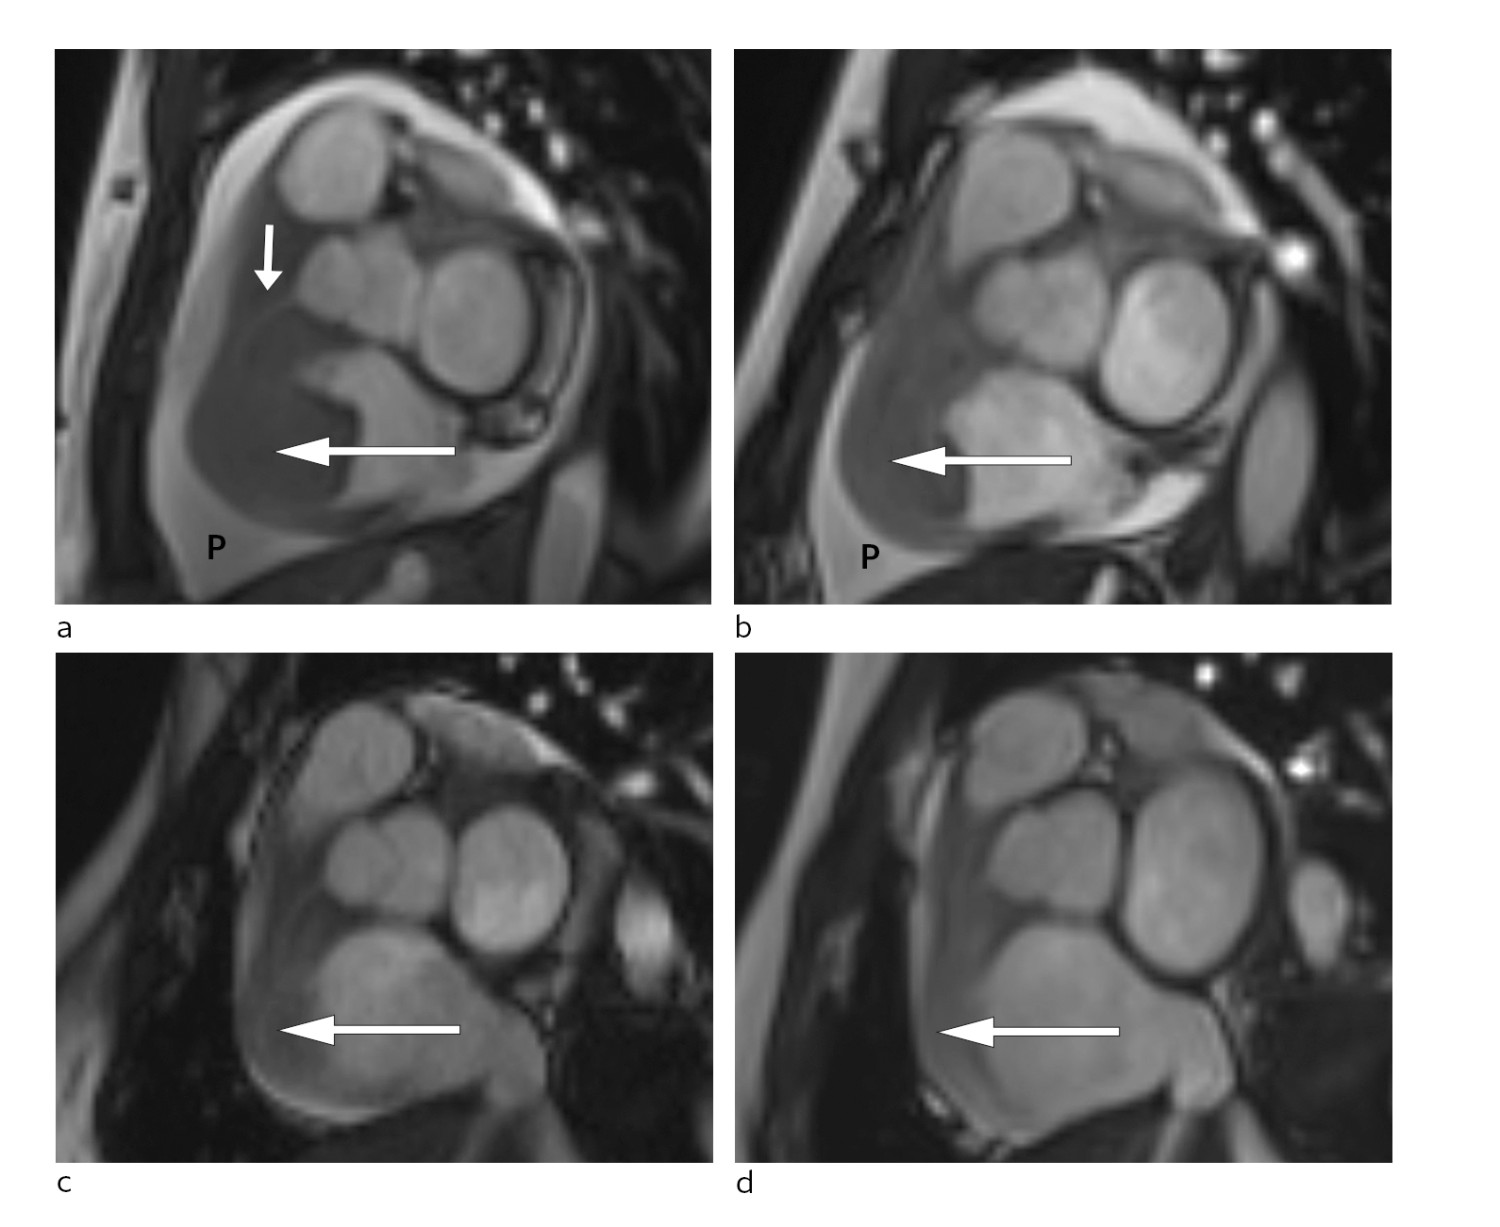

Allereie timar etter at behandlinga tok til merka pasienten avtakande brystsmerter og mindre dyspné. To dagar seinare var det mogleg gjennomføre MR-undersøking av hjartet. Denne bekrefta persisterande tumormassar i høgre atrium og høgre ventrikkel med gjennomvekst av ventrikkelvegg og samanlodding av trikuspidalsegla (fig 3).

Pasienten vart i denne fasen observert i hjarteovervakingsavdelinga. Det vart ikkje observert arytmiar eller andre komplikasjonar til behandlinga. Ho fekk lågdosert fraksjonert heparin som tromboseprofylakse. Repetert MR-undersøking som vart gjort tre dagar etter oppstart med CHOP-regimet, viste betydeleg regress av oppfyllinga i høgre hjartehalvdel og nærast total regress av intrakavitære komponentar. Den atrioventrikulære opninga på høgre side var betydeleg større enn ved den initiale MR-undersøkinga (fig 3).

Pasienten gjennomgjekk ytterlegare blokkurbehandling. Radiologisk evaluering etter andre behandling viste nærast total regress av tumormanifestasjonat i abdomen (fig 3). Ein har heldt fram med R-CHOP-regimet, som har helde sjukdomen i remisjon sidan.